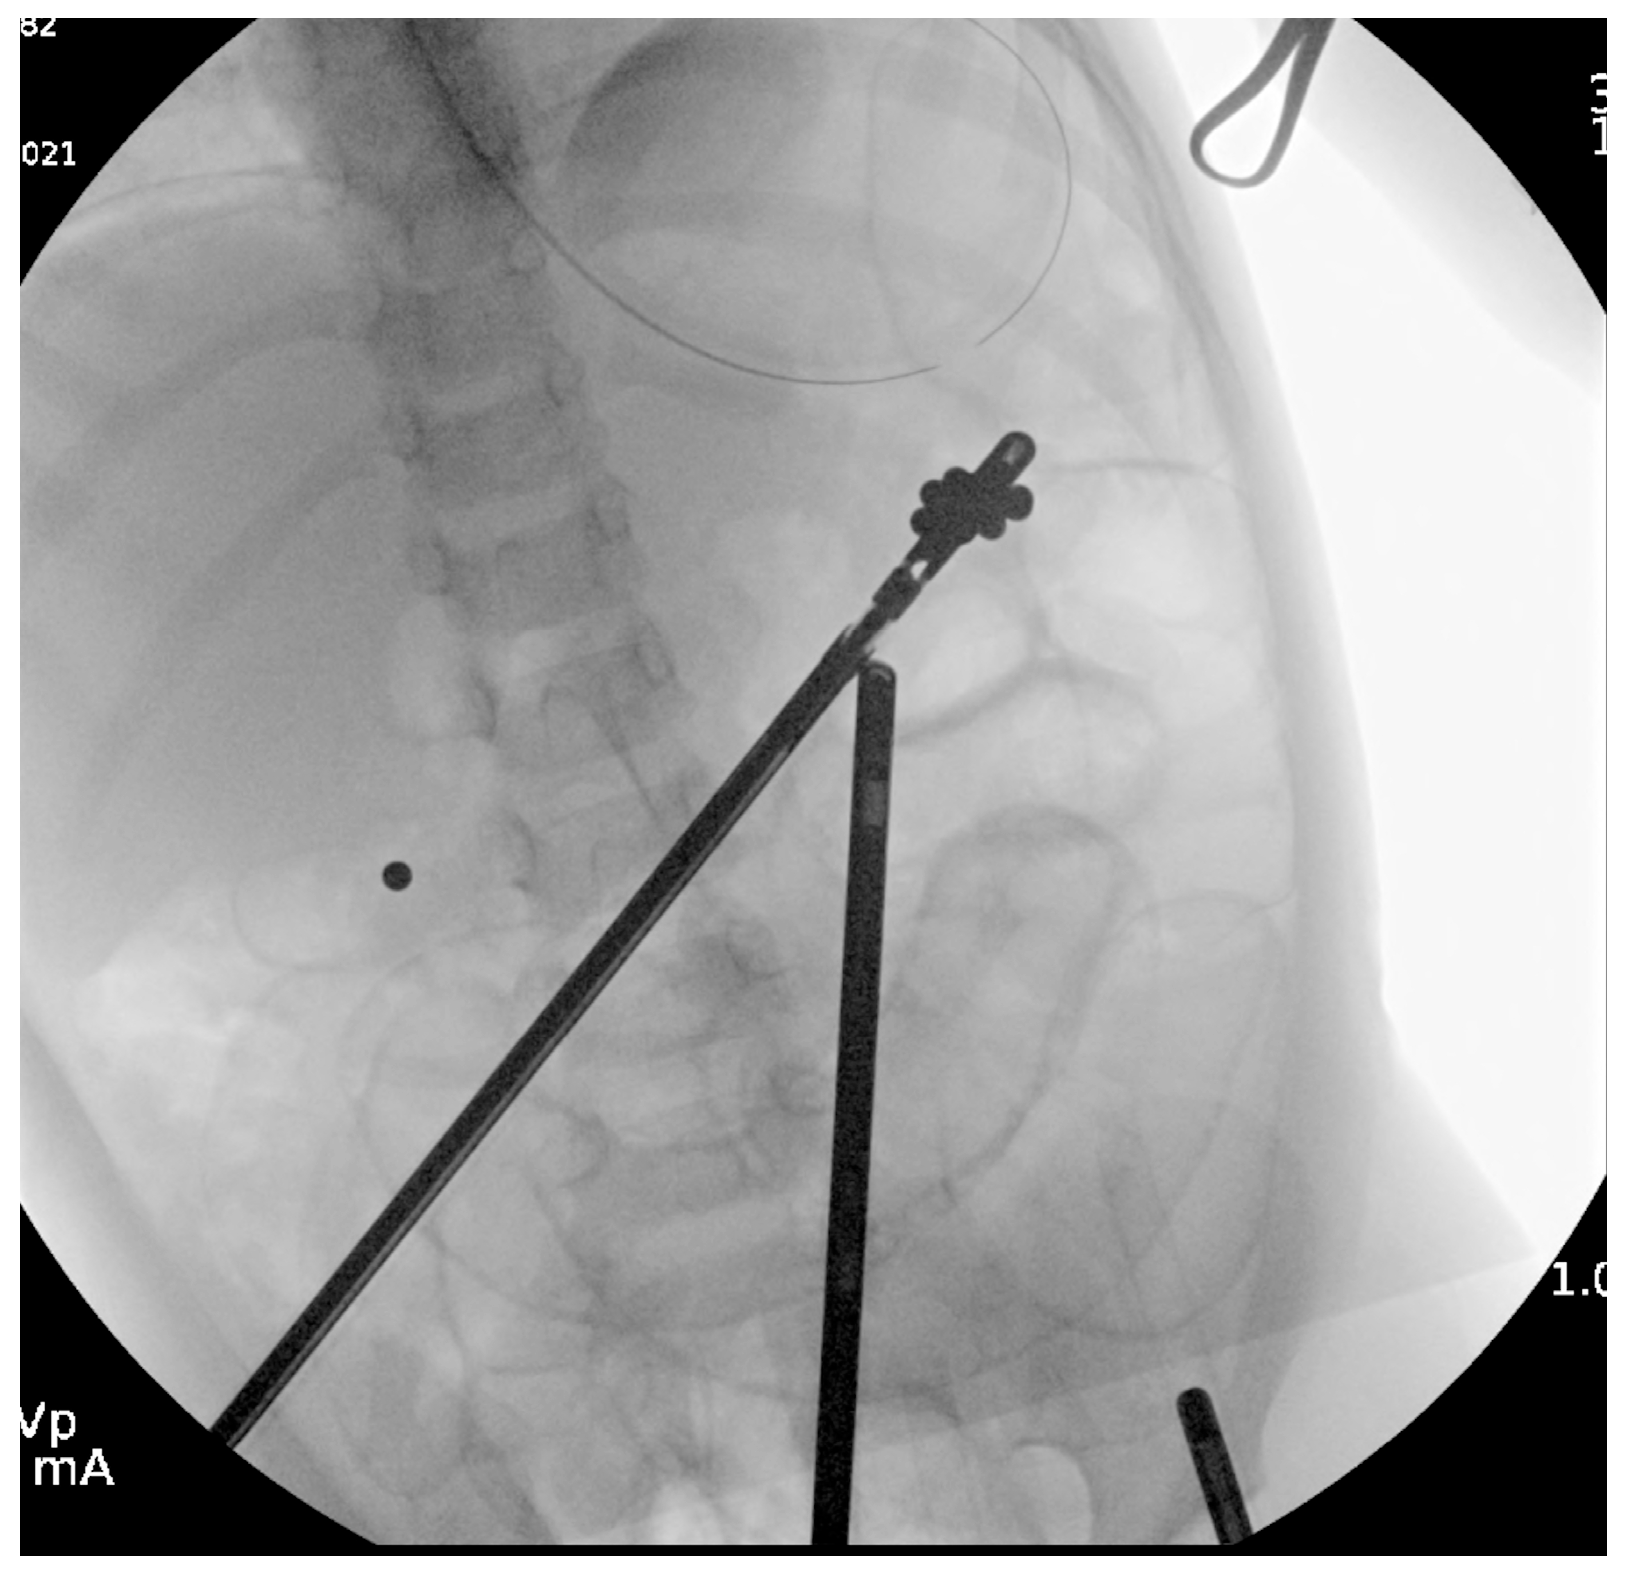

Due to concerning gas patterns 36 h into admission and inability to locate all magnets on imaging, general surgery proceeded with diagnostic laparoscopy. The laparoscopy revealed a single magnet in the hepatic flexure of the colon and a cluster of magnets in the splenic flexure.

Colonoscopy was attempted by pediatric gastroenterology in an unprepped colon to avoid procedural delays. Due to formed stool, retrieval was unsuccessful. A nasogastric tube was placed for MiraLAX-based bowel prep, and serial abdominal x-rays were performed (Figure 4a,b). This approach aligns with conservative management strategies reported in the literature [3,11].

Figure 4. Abdominal radiographs before (a) and after (b) colonoscopy.